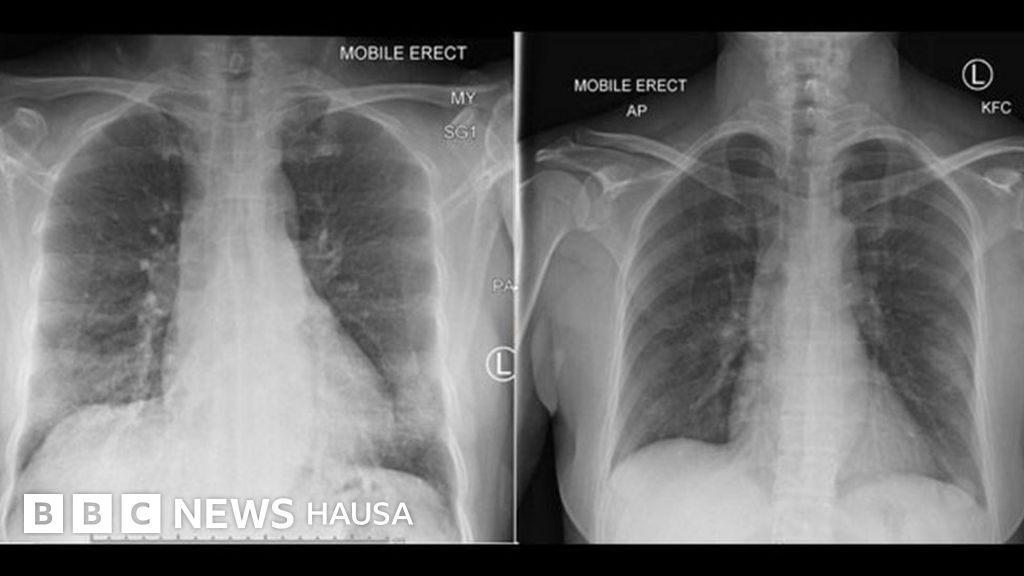

Asalin hoton, PETER DOHERTY INSTITUTE